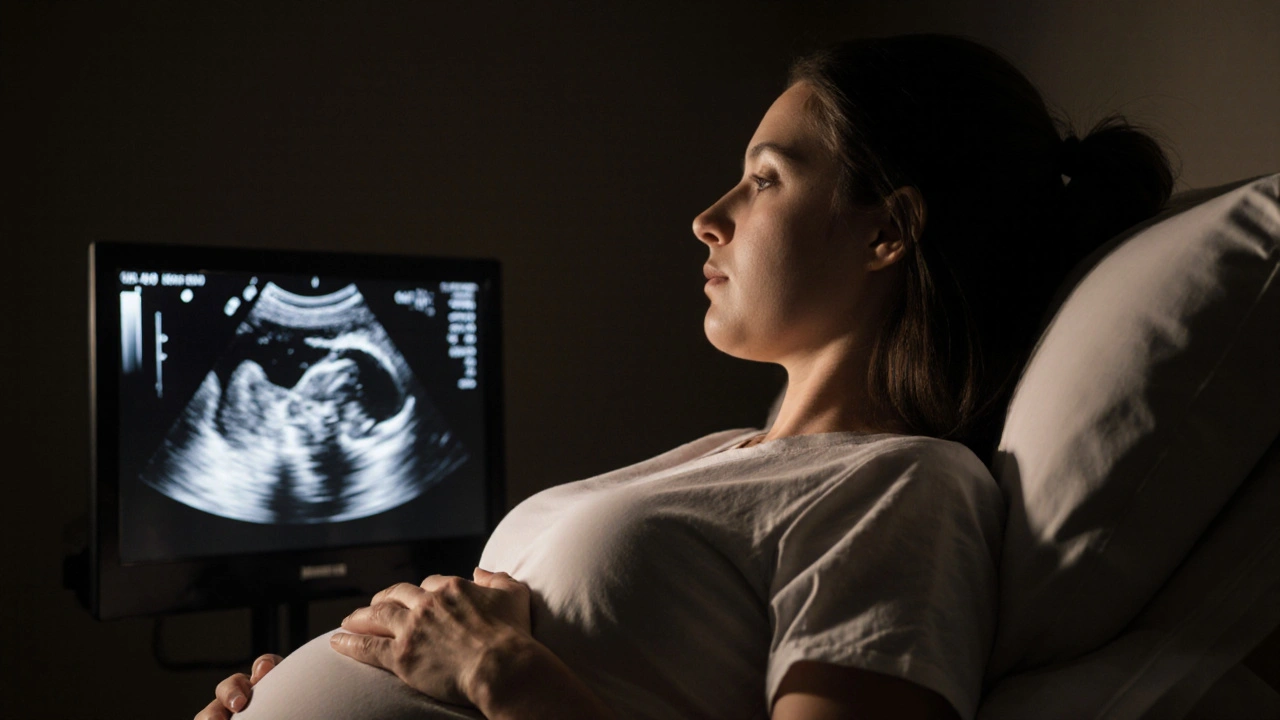

Těhotná žena sleduje ultrazvukový obraz s klidným výrazem tváře.